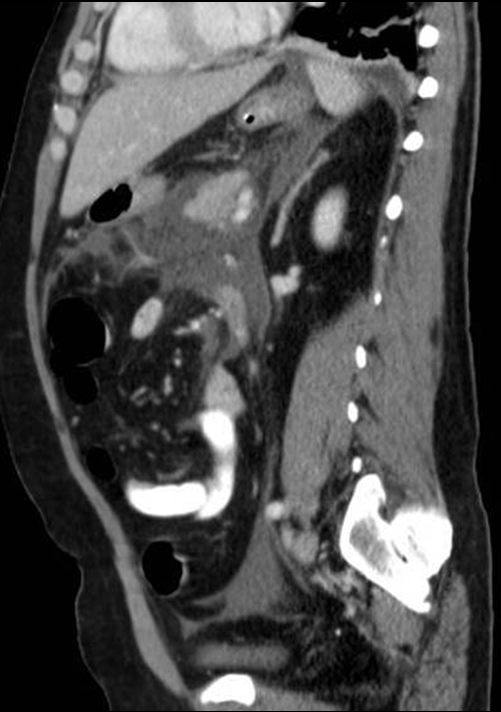

• In the periumbilical region bowel obstruction, acute pancreatitis, early appendicitis, mesenteric thrombosis/embolisation, aorta-aneurysm or diverticulitis can present with pain.

• Abdominal aorta aneurysm or thoracic aorta aneurysm that extends abdominally can both be impending or already completed ruptures. If the patient is stable and is able to cooperate – unless immediately taken to the operation room – has to be assessed with CT angiography. CTA can reveal probable contrast leakage and retroperitoneal hematoma in a matter of a few minutes. In these cases time consuming and non-informative investigations, such as abdominal radiography or ultrasonography can prove to be fatal. Moreover, the pressure is applied with the transducer during sonography, is feared to induce or increase the probability of rupture or bleeding. On average, however when aneurysm or rupture are not considered as the primary diagnoses, routine abdominal US can also be used. Ultrasonography might depict inhomogeneous periaortic hematoma as a hypoechogenic retroperitoneal mass. In these cases one should not hesitate to perform CTA examination, since is the gold standard of abdominal aneurysm.

• Mesenteric thrombosis/ embolism present as continuously increasing, intensive colic-like abdominal pain (mesenteric angina). Plain abdominal radiography can show paralytic obstruction, which in turn, due to the gas filled bowels, can seriously limit the diagnostic use of US. Hence the Sonographic assessment of the retroperitoneum or the Doppler examination of the mesenteric blood vessels cannot be performed. If the there is clinical suspicion of mesenteric thrombosis abdominal CT examination is the method of choice.

22. Colic-like periumbilical pain presents in an elderly patient with generalized atherosclerosis. On the right, CTA examination reveals the occlusion of the superior mesenteric artery about 8 cm from its origin. On the left, 3D reconstruction of CTA examination. Note the extensive aortic sclerosis.